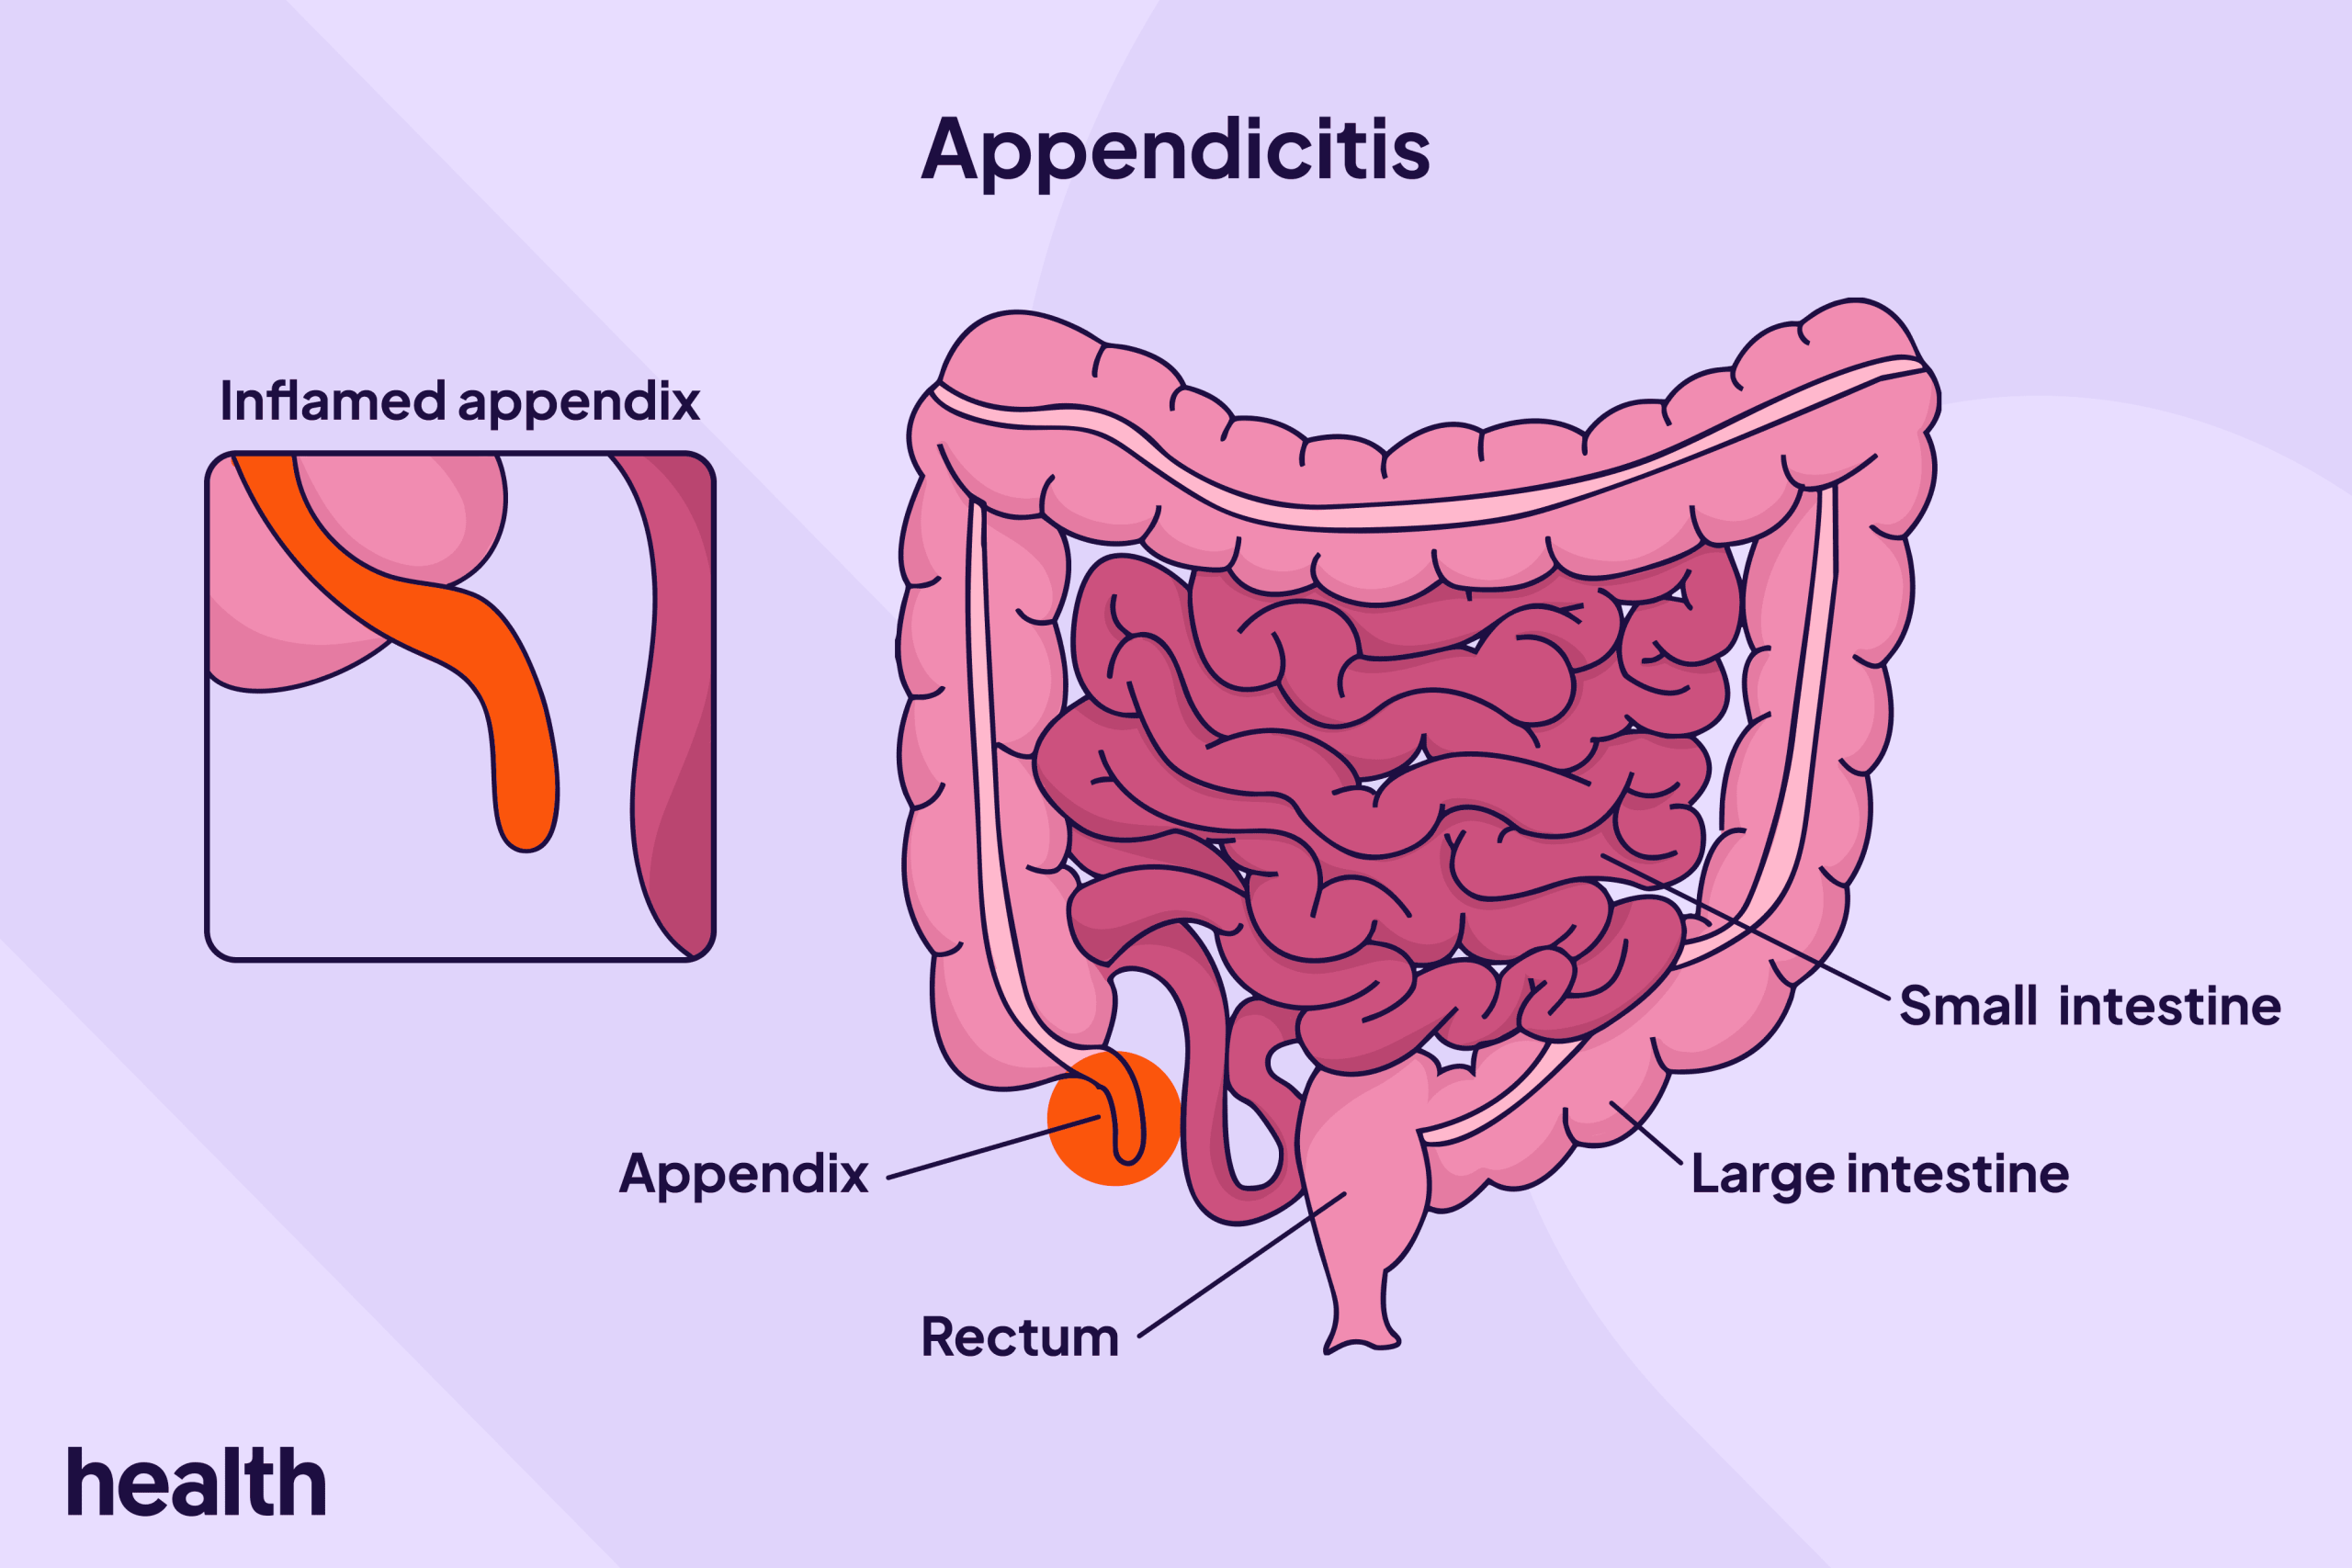

در واقع، آپاندیس به عنوان یک ساختار کیسهای شکل، از سکوم (کور روده) که ابتدای روده بزرگ است، بیرون میآید و به دلیل اهمیت آن در برخی از عملکردهای رودهای، مورد توجه قرار گرفته است.

یکی از مزایای بالقوه جهانی بدون آپاندیس میتواند کاهش موارد آپاندیسیت باشد. برآوردها نشان میدهد که در سطح جهانی هر سال بیش از ده میلیون مورد آپاندیسیت گزارش میشود و تا 50 هزار نفر جان خود را به سبب آن از دست میدهند.

برداشت آپاندیس از طریق جراحی، به عنوان یکی از عمومیترین جراحیهای شکمی شناخته میشود. در صورت عدم وجود آپاندیس، افراد دیگر به علت آپاندیسیت جان خود را از دست نمیدادند و هزینههای مرتبط با جراحی و بستری نیز وجود نداشت.